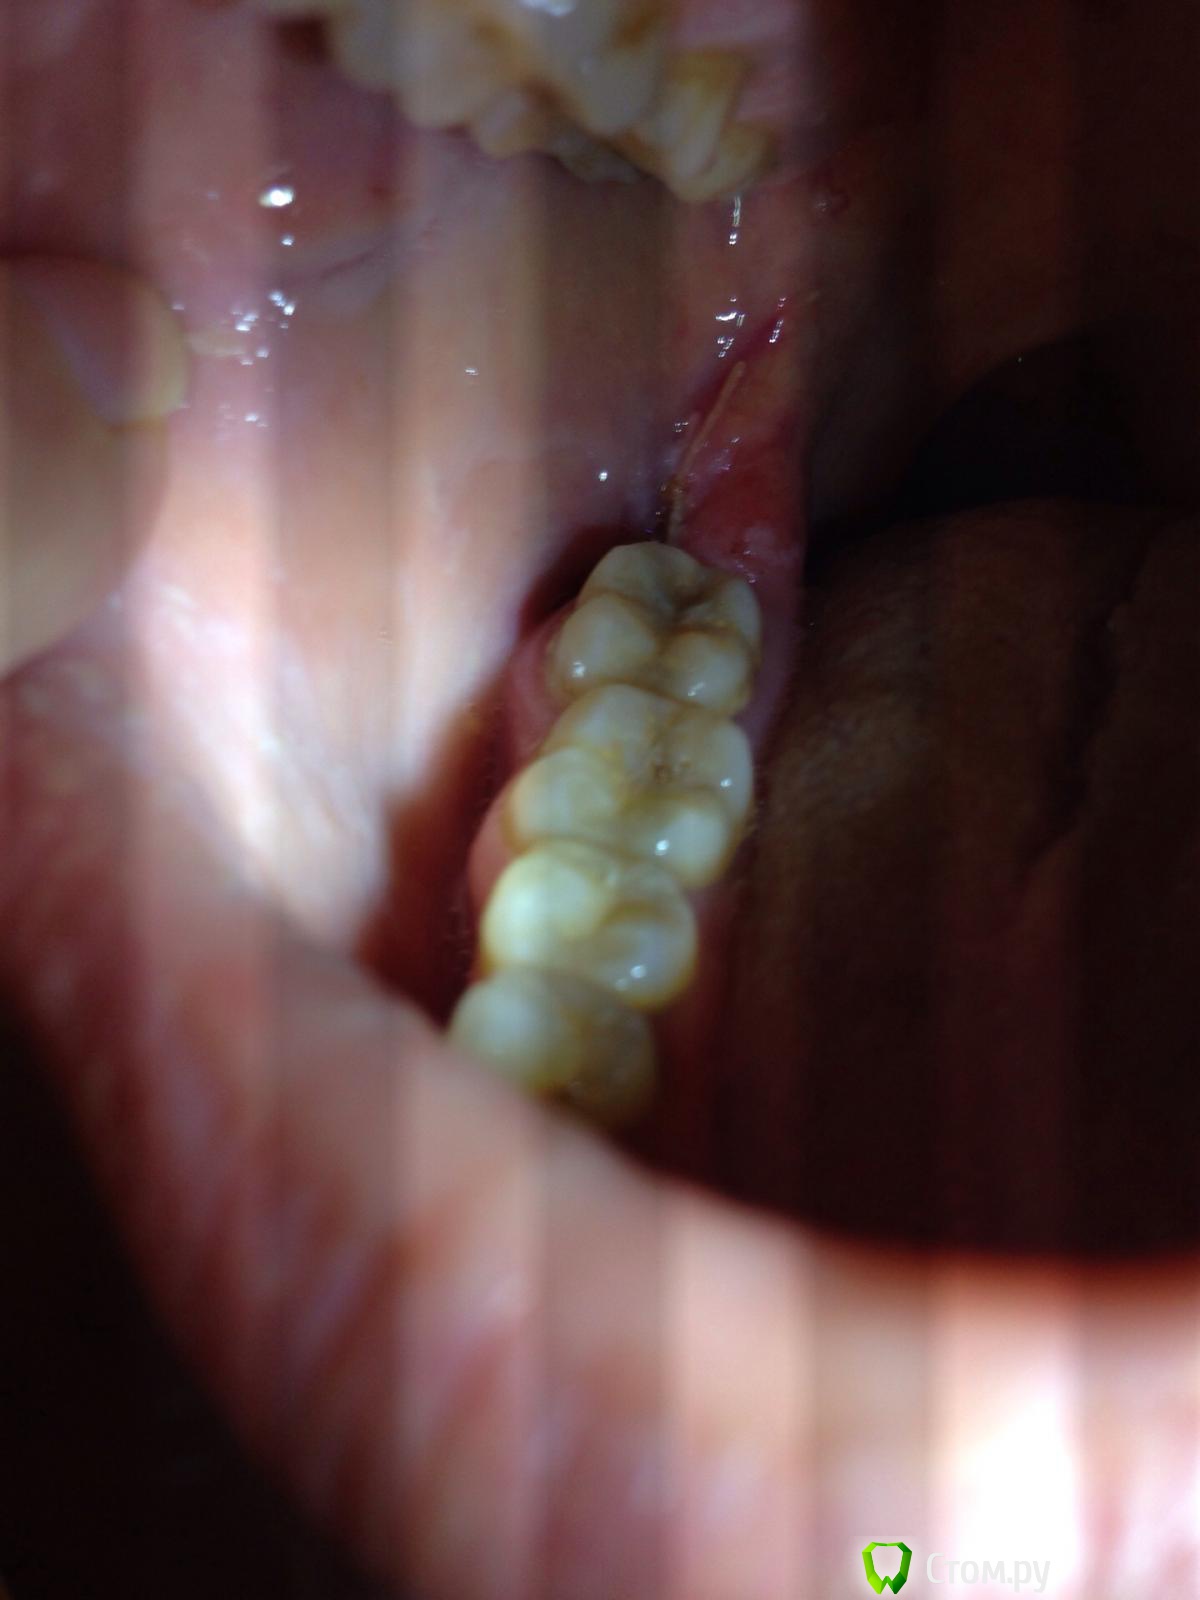

IvanK Опубликовано 17 ноября, 2014 Поделиться Опубликовано 17 ноября, 2014 Думаю, что Вы зря паникуете. Сделайте фото 1 Ссылка на комментарий

Irson Опубликовано 17 ноября, 2014 Автор Поделиться Опубликовано 17 ноября, 2014 Фото Ссылка на комментарий

Irson Опубликовано 18 ноября, 2014 Автор Поделиться Опубликовано 18 ноября, 2014 Здравствуйте! Сегодня второй день, в лунке что то беленькое. Не полоскала, ела только жидкую кашу и чай. Вчера прикладывала марлевые тампоны для остановки кровотечения, могла ли я ими повредить сгусток? Пока сильной боли нет, анальгетики не пила, только очень больно глотать со стороны удаленного зуба. Температуры и отека нет. Периодически чувствую что то соленое во рту, неприятного запаха нет.Пожалуйста, не оставьте без внимания. Переживаю, все ли идет нормально, так как в понедельник у меня командировка, боюсь не восстановлюсь за неделю. Ссылка на комментарий

red_butler Опубликовано 18 ноября, 2014 Поделиться Опубликовано 18 ноября, 2014 По Вашему описанию, все нормально, белое - это фибринозный налет. В чем проблема показаться своему врачу и успокоиться? 3 Ссылка на комментарий